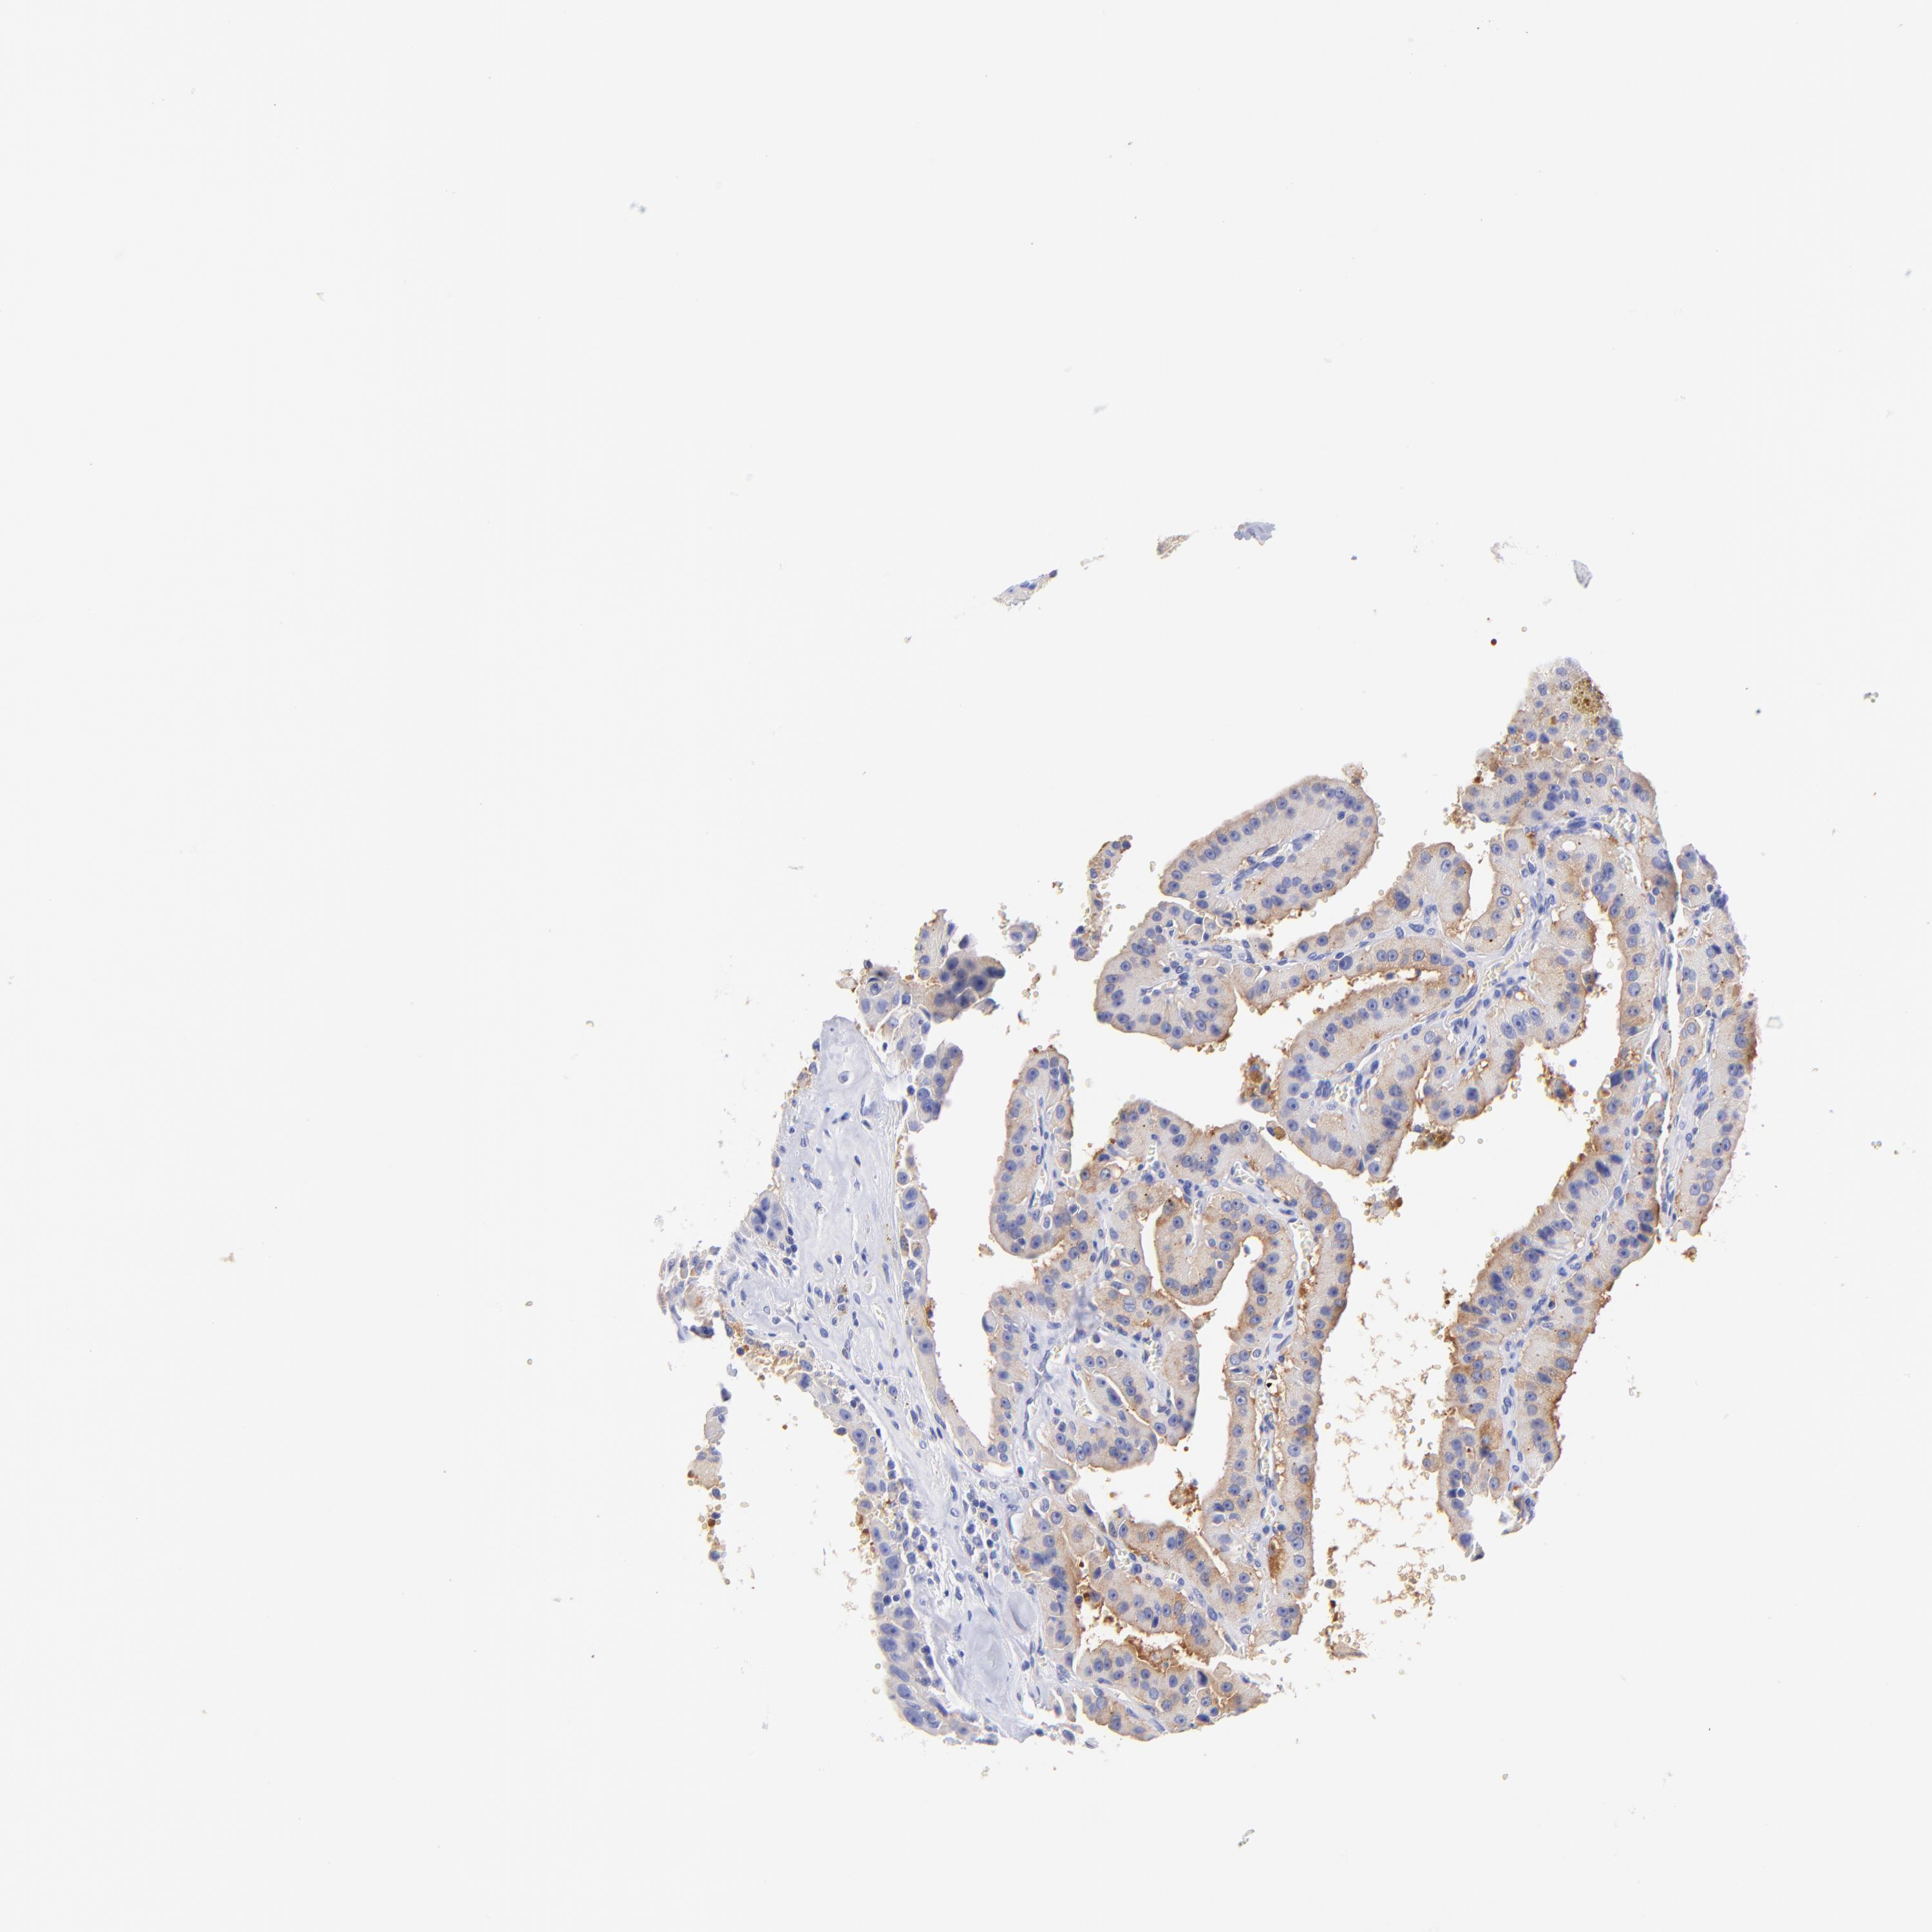

THYROID CANCER - Protein expressioni

A mouse-over function shows sample information and annotation data. Click on an image to view it in a full screen mode. Samples can be filtered based on level of antibody staining by selecting one or several of the following categories: high, medium, low and not detected. The assay and annotation is described here.

Note that samples used for immunohistochemistry by the Human Protein Atlas do not correspond to samples in the TCGA dataset.

Antibody stainingi

Antibody staining in the annotated cell types in the current human tissue is reported as not detected, low, medium, or high, based on conventional immunohistochemistry profiling in selected tissues. This score is based on the combination of the staining intensity and fraction of stained cells.

Each image is clickable and will lead to virtual microscopy that enables deeper exploration of all samples and also displays staining intensity scores, fraction scores and subcellular localization as well as patient and tissue information for each sample.

Antibody HPA003116

Antibody HPA024694

Antibody CAB004419

Staining

High

Medium

Low

Not detected

Intensity

Strong

Moderate

Weak

Negative

Quantity

>75%

75%-25%

<25%

None

Location

Nuclear

Cytoplasmic/membranous

Cytoplasmic/membranous,nuclear

Carcinoma, NOS

Follicular adenoma carcinoma, NOS

Papillary adenocarcinoma, NOS